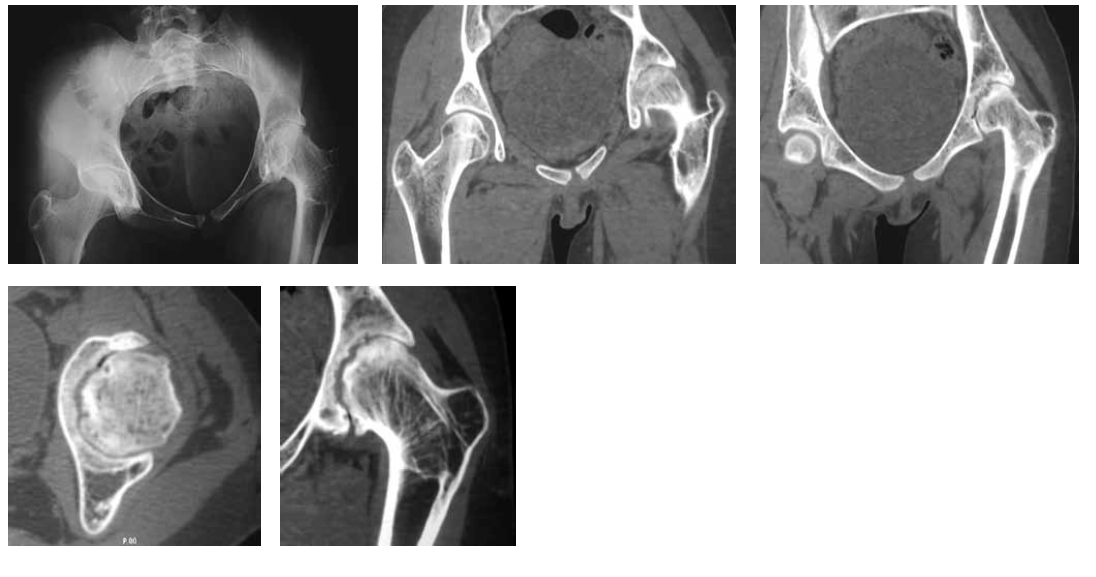

Radiography and computed tomography of the hip joints (Fig. 2) showed that on the left, the femoral head was deformed and had an irregular shape and uneven contour. The contour of the acetabulum was uneven. The joint gap was sharply narrowed and was not traced in some places. The diagnosis was a consequence of septic coxitis, secondary deforming coxatrosis on the left, and fibrous ankylosis of the left hip joint. Considering the clinical and radiological picture, the pronounced vicious position of the lower limb, the absence of pain syndrome, and early adolescence, we decided to conduct a stepwise organ-preserving complex treatment aimed at eliminating the vicious position of the limb by eliminating the fibrous block between the articular surfaces with subsequent development of movements in the hip joint. The treatment plan included a combination of the following modern methods: distraction in the device, arthroscopy, intra-articular injections, therapeutic exercises and other rehabilitation measures. The first stage (Fig. 3) for the expansion of the joint space involved the imposition of a wire-rod distraction apparatus of the MKC on the pelvic bone and the left hip with spinal adductomy.

Fig. 2. Radiograph and computed tomography (CT) scan of the hip joints. Deforming coxatrosis. The femoral head is deformed, has an irregular shape, and has an uneven contour. The cotyloid cavity also has an uneven contour. Joint space is sharply narrowed and is wavy because of the closure of the articular surfaces of the head and cavity of “puzzle” type. Degenerative-dystrophic changes in the form of areas of subchondral sclerosis, cystic changes, and marginal bone growths. Adduction contracture at an angle of 40°